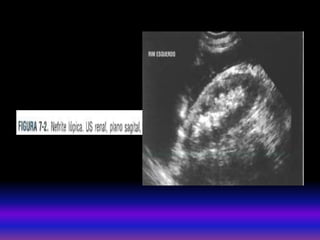

• MEDICINA NUCLEAR Cintilografiarenal com DMSA util para avaliação da função renal e perfusão sanguínea renal. DMSA 99mTc É muito sensível para demostrar cicatrizes renais. • BIOPSIA PERCUTANEA RENAL Guiada por US. Útil para pacientes com diagnostico incerto após investigações. Não é indicada em rins fibróticos ( pequenos e hiperecogênicos), diátese hemorrágica incontrolável , HTA grave não controlada, hidronefrose e infecção renal ativa. MÉTODOS DE IMAGEM